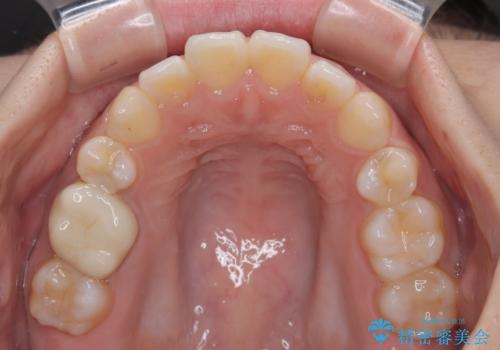

再矯正 開咬に後戻りした歯列をインビザラインで改善

- 矯正治療の後戻りを気にして来院された患者様です。

デコボコと上下前歯の隙間が気になるものの、しっかりと治療をしたいという意思はないとのことで、インビザラインの中でもアライナー数に制約のあるライトパッケージを用いて、治療できる範囲まで歯列を改善していくこととしました。

インビザラインは前歯部の開咬に効果的であることが多く、ライトパッケージにもかかわらず、十分満足のいく仕上がりとなりました。